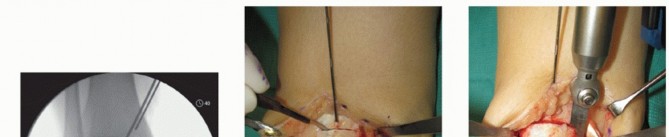

Anterior ankle arthrotomy (TECH FIG 1A)

Defines anterior joint margin for safe performance of medial malleolar osteotomy

Allows partial visualization of the OLT and allows confirmation that there is no diffuse articular cartilage degeneration

Open the posterior tibial tendon sheath-flexor retinaculum, directly on the posterior margin of the tibia and medial malleolus (TECH FIG 1B). Protect the posterior tibial tendon: It rests in a groove immediately posterior to the tibia and is at great risk with a medial malleolar osteotomy.

- TECH FIG 1 • A. Medial incision and anterior ankle arthrotomy. B. Opening of the posterior tibial tendon sheath. C. Predrilling of medial malleolus. Kirschner wire for trajectory of medial malleolar osteotomy has already been inserted and its position confirmed with fluoroscopy. D. Fluoroscopic image demonstrating Kirschner wire being used as a guide to direct the saw. E. The periosteum is scored perpendicular to the tibial shaft, at the level of the osteotomy. F. Medial malleolar osteotomy. Care must be taken to protect the posterior tibial tendon. (continued)

Predrill the medial malleolus across the proposed osteotomy site (TECH FIG 1C).

We routinely use two small fragment malleolar screws and predrill with the corresponding drill. Obtain fluoroscopic confirmation that the drill bits are in the proper trajectory.

Place a Kirschner wire obliquely to define the trajectory of the medial malleolar osteotomy (TECH FIG 1C).

Place it slightly proximal to the desired osteotomy so it can function as a guide but not interfere with the saw (TECH FIG 1D).

Confirm the optimal Kirschner wire trajectory with intraoperative fluoroscopy.

Determine a plane for the osteotomy in the anteroposterior (AP) plane that is perpendicular to the longitudinal axis of the tibia. We find it helpful to score the osteotomy in the periosteum from anterior to posterior to determine this level (TECH FIG 1E).

With a microsagittal saw oriented correctly in both planes, the osteotomy is initiated (TECH FIG 1F).

Obtain intraoperative fluoroscopy shortly after initiating the osteotomy; leave the saw blade in place to confirm proper trajectory. If incorrect, a subtle adjustment is still possible (TECH FIG 1G).

Continue the osteotomy with the saw to the subchondral bone and then complete the osteotomy with a chisel.